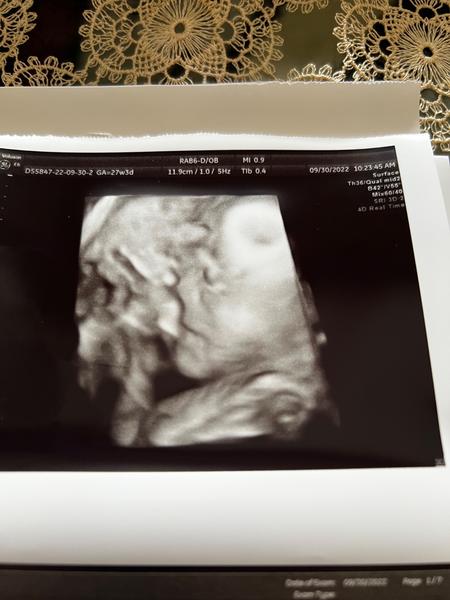

Odpovídá 4D ultrazvuk reálnému obrazu plodu?

Zdravím, včera jsem byla na 4D ultrazvuku. Jsem v 28.týdnu, vzhledem k tomu, že mám placentu na přední straně, tak ten obraz nebyl nejlepší.

Prý má 1kg. Přijde Vám, že je na svoje ,,stáří” dost malinký? Na 4D ultrazvuku jsme byla poprvé a nevím ,jak moc tedy obraz odpovídá realitě. Podle obrázku to vypadá, že prakticky nemá žadné rtíčky.😅

Malinký mi nepřijde, nejvíc se nabírá v posledním trimestru, kdyby bylo něco špatně, tak by to Dr určitě řešil. Jinak odpovídání vzhledu i celkem sedí, je to takové kostrbaté, ale třeba nos a rty na těch 3D fotkách moje děti měly už jako při narození :D